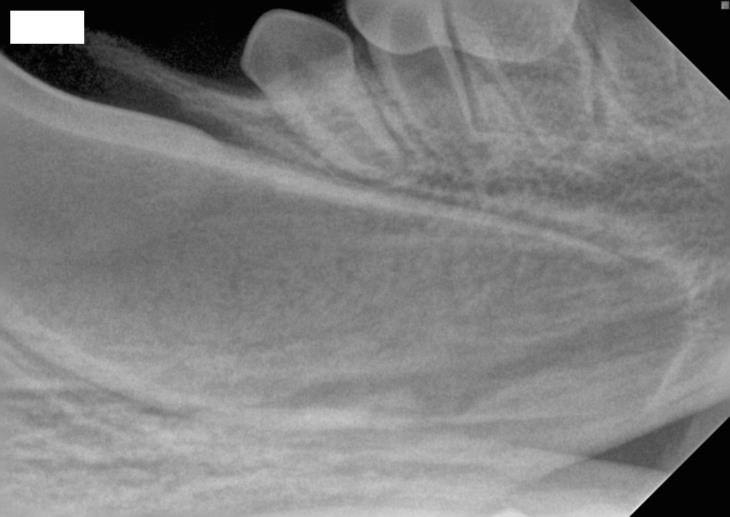

Fig 2: Radiograph of immature tooth root, the root canal is extremely wide, the dentinal walls thin and there is no formed root apex.